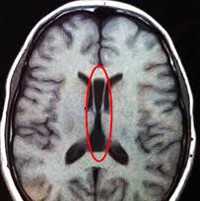

Одним из методов выявления пороков головного мозга у грудничков является нейросонография через родничок. Намного более точные данные у детей любого возраста и у взрослых получают при помощи МРТ головного мозга. МРТ позволяет определить характер и локализацию аномалии, размеры кист, гетеротопий и других аномальных участков, провести дифференциальную диагностику с гипоксическими, травматическими, опухолевыми, инфекционными поражениями мозга. Диагностика судорожного синдрома и подбор антиконвульсантной терапии осуществляется при помощи ЭЭГ, а также пролонгированного ЭЭГ-видеомониторинга. При наличии семейных случаев церебральных аномалий может быть полезна консультация генетика с проведением генеалогического исследования и ДНК-анализа. С целью выявления сочетанных аномалий проводится обследование соматических органов: УЗИ сердца, УЗИ брюшной полости, рентгенография органов грудной полости, УЗИ почек и пр.

Обязательными являются инструментальные методы, позволяющие визуализировать костные деформации и оценить степень поражения тканей головного мозга. Сюда относятся нейросонография, рентгенография, компьютерная и магнитно-резонансная томография. Нейросонография используется с целью оценить состояние тканей головного мозга и размеры желудочков, выявить внутричерепную гипертензию. На рентгенограмме удается определить нарушения структуры костей, окостенение черепных швов, а при повышенном внутричерепном давлении - усиление пальцевых вдавлений. КТ и МРТ применяются для получения более информативных результатов. При подозрении на поражение зрительной системы проводится офтальмоскопия, позволяющая обнаружить поражение диска зрительного нерва. Рекомендованы консультации нейрохирурга и офтальмолога.